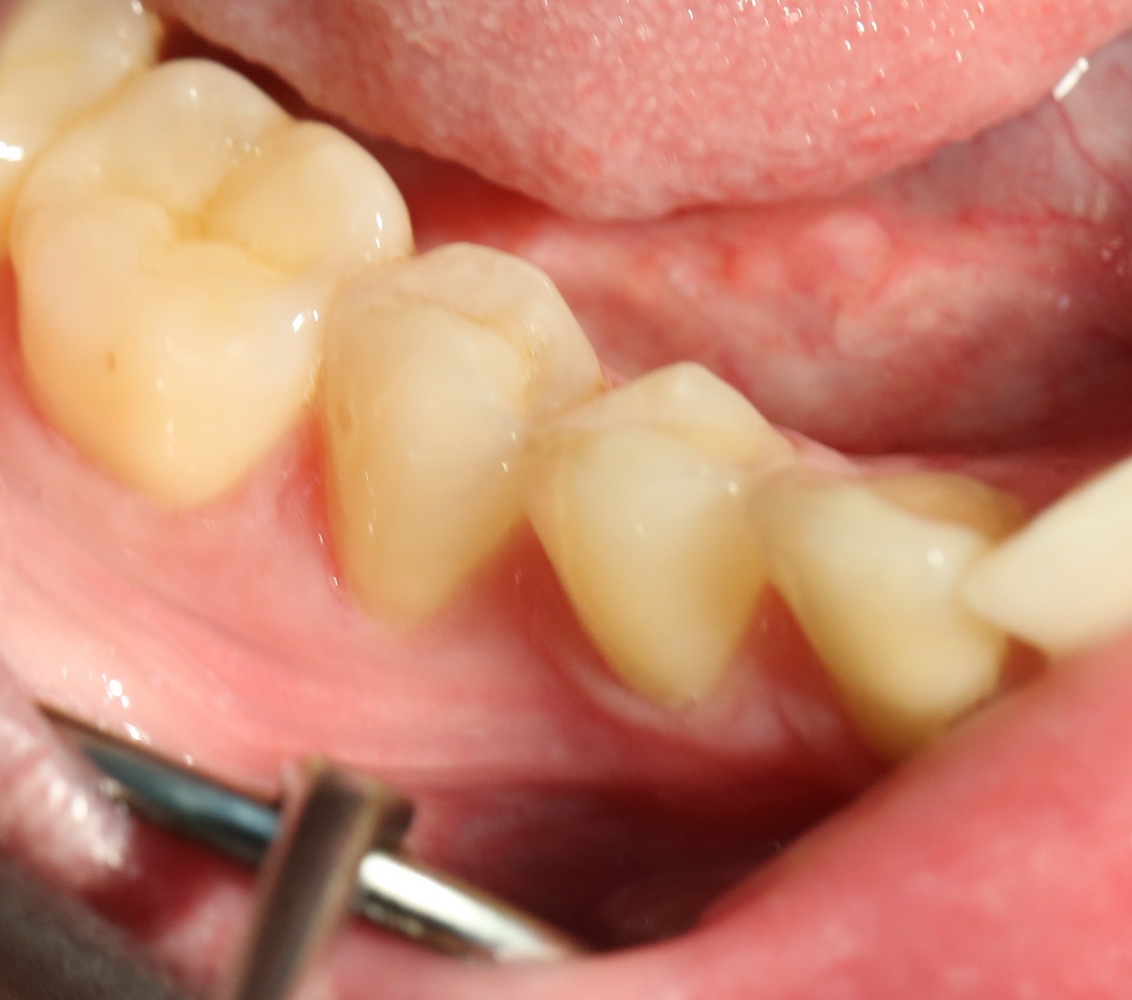

Вот фотография послеоперационной раны через пару дней:

Так, друзья, выглядит нормальная послеоперационная рана. Со швами я угадал. Это, кстати, Prolene 5-0.

А вот фотография через месяц после операции:

Задайтесь вопросом — оно того стоило? 30 минут в операционной, 4 дня на реабилитацию и 2 недели со швами? Стоило ли это того, чтобы в будущем избежать серьезных проблем со здоровьем?

На мой взгляд — да.